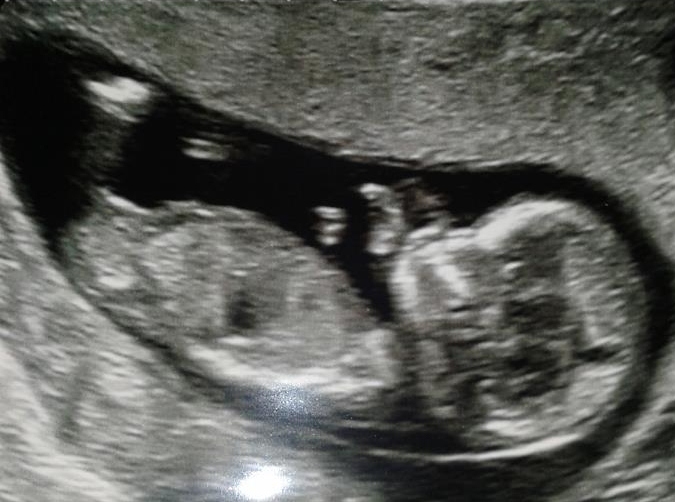

This is my Sister in law's ultrasound photo, 12 weeks and 4 days, I'm thinking DEFO a girly right? I do have her permission to post on here. She is desperate to know!!

Attachment 8755

i woulda given a slight boy lean, though at the same time I'd expect more angle at almost 13 weeks. I'm not sure. I'd go boy, 60%

Girl, has a bit of a boy shape but often girls do at this stage and kind of angles up ever so slightly at the end which kind of throws me a tiny bit. BUT the angle on a whole is very flat so I really think this baby is a girl.